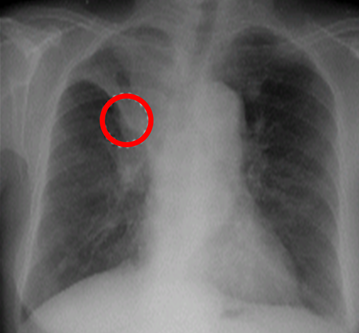

Complicated Right Upper Lobe Atelectasis Caused By A Large Hilar Mass Forming The Reverse S Sign Of Golden Lymphoma Images Diagnosis Treatment Options Answer Review Thoracic Imaging

The Golden S Sign Right Upper Lobe Collapse Radiologypics Com